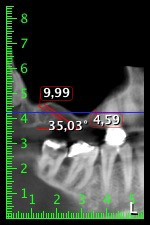

Etwa sechs Monate nach Extraktion der Zähne 16 und 14 wurde zur Planung und Risikominimierung eine digitale Volumentomografie (DVT, Planmeca) erstellt. Hierbei wurde deutlich, dass der Knochen sich nicht in der gewünschten Quantität regeneriert hat (Abb. 2 bis 7).

Um die Augmentation auf Regio 14 einzuschränken, wurde in Absprache mit der Patientin eine Schrägstellung des Implantats 16 nach dorso-kranial geplant (Abb. 8).